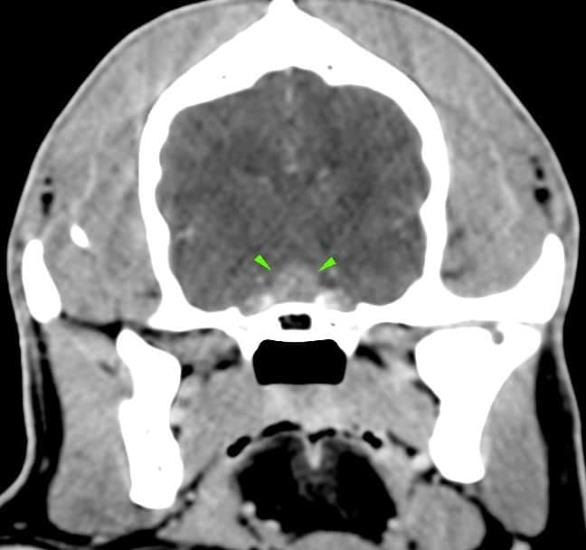

A 8-year-old cocker spaniel was referred for polyuria/polydipsia and polyphagia. The abdominal ultrasound revealed bilateral symmetric adrenal enlargement (images below). A CT scan of the head was performed. A round, 7mm, contrast-enhancing nodule was found at the level of the pavement of the sella turcica, in the hypophyseal fossa (green arrowheads).

A final diagnosis of pituitary-dependent hyperadrenocorticism was made.